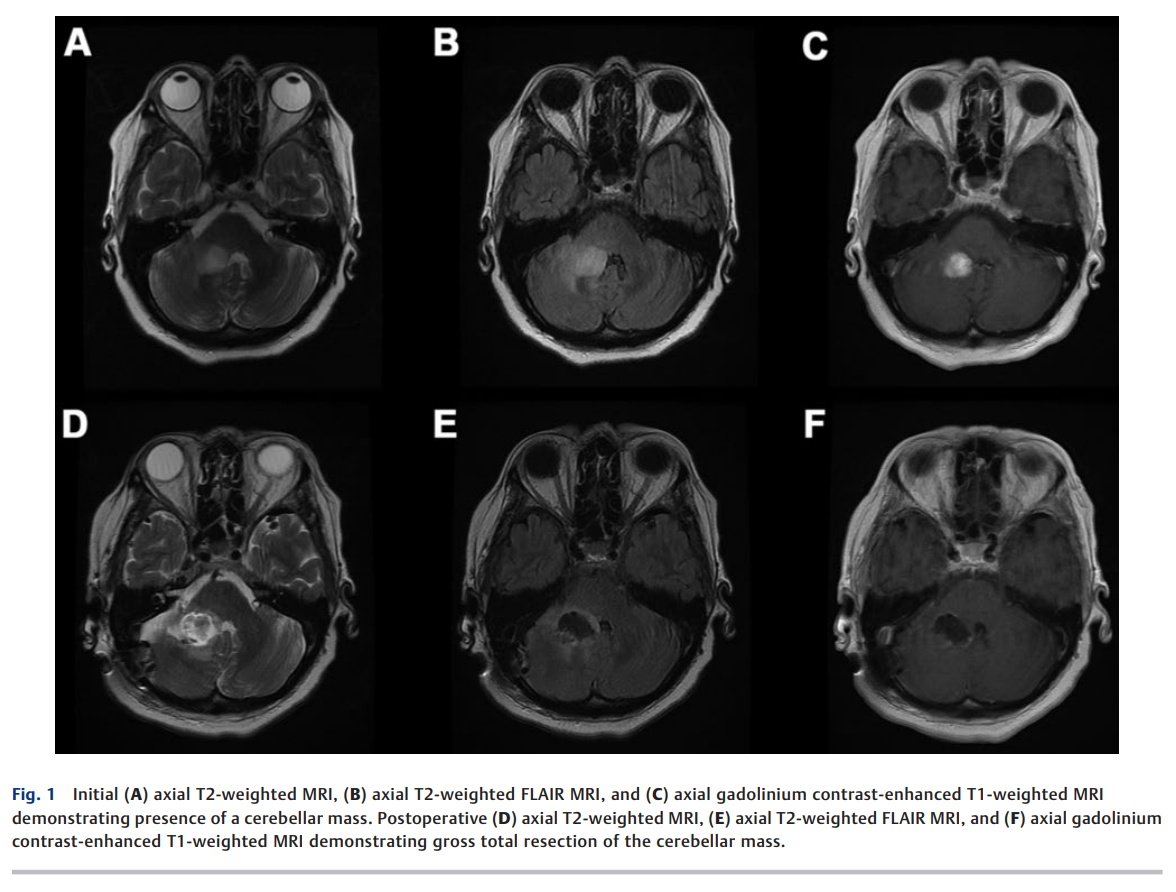

Intracranial Retrograde Cerebrospinal Fluid Dissemination of H3 K27-altered Glioma

弥漫性中线胶质瘤,H3 K27 改变型(DMGHA),是一种少见的原发性恶性脑肿瘤,预后不良且治疗选择有限。我们报告一例独特病例:一名老年女性最初因右侧小脑 DMGHA 接受治疗,随后在透明隔处出现远处复发,推测其原因为脑脊液(CSF)逆行性播散。